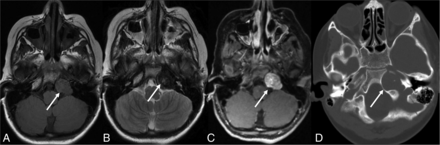

EBV is a rare cause of encephalitis in children and immuno-competent adults. The most common presentations are fever (81%), headache (66%), and seizure (10%).11 MR imaging is preferred for suspected encephalitis, with abnormalities found in 27.6%–80% of patients (Fig 1). Vyas et al12 reported abnormal findings on brain imaging in 29/45 (64.5%) pediatric patients. Cortical/subcortical (20%), white matter (15.5%), and basal ganglia (11%) involvement were more common, followed by the thalamus (9%), brainstem (6.2%), substantia nigra (4.4%), cerebellum (4.4%), and spinal cord (3%). Diffusion restriction and susceptibility changes were seen in 24.4% and 15.5% of cases, respectively. Meningeal involvement was reported in 5%–22%.9,12 Brain abscess, subdural effusion/empyema, and hemorrhage are rare.12

EBV meningoencephalitis in a patient with infectious mononucleosis. CSF was positive for EBV. Axial T2 FLAIR (A and B) images show multifocal areas of hyperintensity mainly within the subcortical white matter of the bilateral cerebral hemispheres (arrows) without diffusion abnormalities on axial DWI (C). Postcontrast axial T1-weighted image (D) shows diffuse leptomeningeal enhancement. The patient was fully recovered on follow-up.

Most patients fully recover without sequelae, while 5%–10% of cases may be fatal.4,11,25,26 For unclear reasons, patients with isolated hemispheric involvement generally have better prognoses. Similarly, about one-half of the patients with thalamic involvement have persistent deficits, while isolated brainstem involvement has a high mortality rate.9,11 EBV encephalitis in immunocompromised patients may occur secondary to latent virus reactivation or a primary infection after transplantation.27,28 The clinical and imaging manifestations are broadly similar, though cases with hemorrhage, ring enhancement, and masslike lesions may also be seen.27⇓-29 Correction of underlying immunosuppression is the mainstay of therapy.